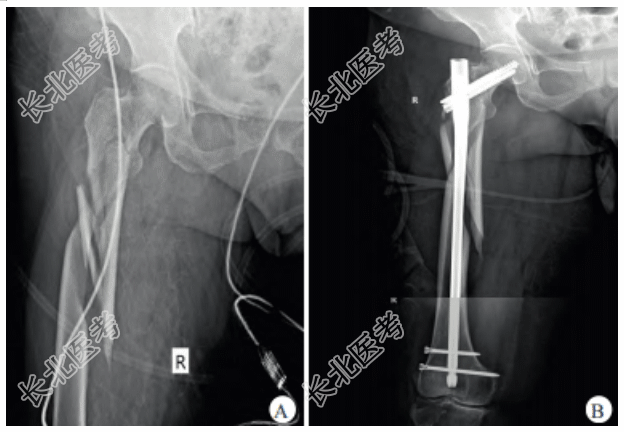

- [材料题] 患者,女,66岁,车祸致腰背部、腹部、右下肢疼痛1h。既往史:高血压病史5年,规律服用降压药,血压控制良好。查体:右大腿肿胀明显伴外旋、短缩畸形,皮肤完整无破损,大腿中上段压痛明显,髋关节活动受限;左肩背部软组织略肿胀,可见皮肤淤血,压痛明显,左肩关节活动轻度受限;腰部软组织未见明显异常,腰椎棘旁压痛明显。X线检查:左肩胛颈骨折、多发腰椎横突骨折、右股骨转子下粉碎性骨折(图1A)。

患者经对症支持治疗后生命体征趋于平稳,为便于多发伤后续诊治及护理,减少患者搬运及体位变动过程中骨折所致副损伤,经多学科会诊讨论后决定行右股骨转子下骨折手术治疗。患者经支持治疗后生命体征恢复平稳,但血红蛋白、血小板及白蛋白仍处于较低水平,应避免过大的手术创面,故手术方案拟选择闭合复位InterTAN髓内钉固定术。术后因患者体位难以配合,仅行右股骨正位X线检查,示InterTAN髓内钉位置良好,但骨折断端仍残留间隙(图1B)。由于患者转子下骨折粉碎严重,术后骨折断端残留明显间隙,为避免内固定松动移位,术后8周患肢开始部分负重功能锻炼,术后3个月患者可扶拐行走,术后5个月复查X线片示InterTAN髓内钉位置良好,骨折端形成骨痂(图2A、图2B)。术后21个月,患者主诉正常行走时无明显诱因出现右髋部疼痛伴活动受限、无法行走。右股骨正侧位X线检查示髓内钉主钉、加压螺钉及远端锁钉均出现断裂(图2C、图2D);进一步行去金属伪影CT检查,示股骨颈干交界部位骨折不愈合(图2E)。